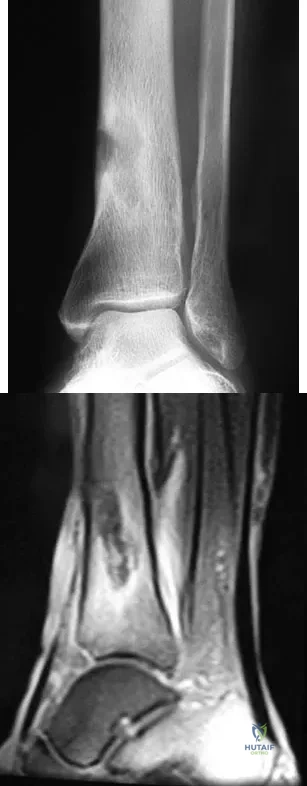

A 45-year-old woman sustains an injury to her lower leg. Examination reveals that there is a deformity with no neurologic or vascular problems. The skin is intact. Radiographs are shown in Figures 46a and 46b. Which of the following factors would make closed management the least appropriate choice for this injury?